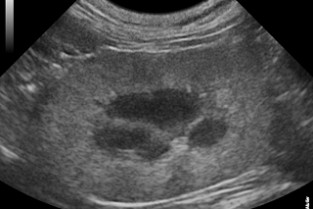

Imagerie du rein: normal - pas normal ?

Hugues Gaillot

Néphropathies congénitales : diagnostic (imagerie, tests génétiques)